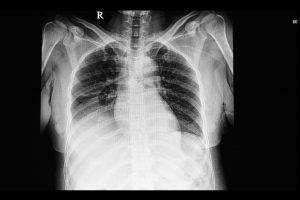

HOME   ·  Pleural infection study points to earlier targeted…   ·  …